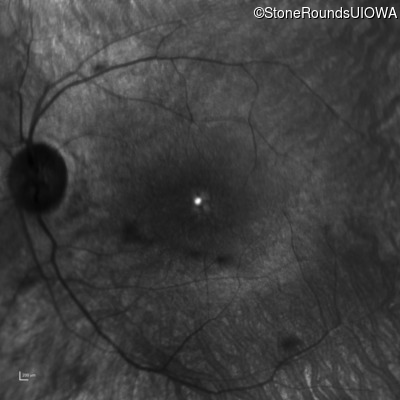

Retinitis Pigmentosa with Anemia (IB10)

OD

OS

20/40 -1

20/32 -2

Age at visit:

18 years

Retinitis Pigmentosa with Anemia

TRNT1

IVS5-26 T>C

Lys416 ins1tggA

AR